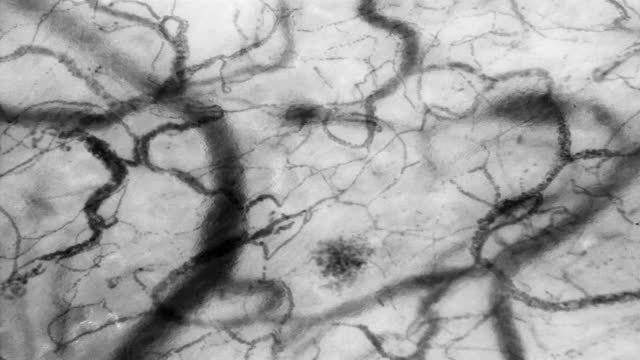

In the early phase of severe sepsis and septic shock, a significant decrease in vessel density and in proportion of perfused capillaries has been reported as compared to control subjects in sublingual videomicroscopy studies16,17 (Fig. 2. See supplementary material at the web). Furthermore, an increase in heterogeneity of vascular density and blood velocity between coexisting areas was also observed in these studies. In addition, these alterations were more severe in non-survivors and the rapid resolution of these microcirculatory changes following interventional therapy was also correlated with improved outcome, including mortality.16,18,19 Conversely, the persistence of these microcirculatory alterations after the first 24h was strongly and independently correlated with mortality secondary to circulatory failure in the early phase, and to multi-organ failure in the late phase.20

Cytocam-Incident Dark Field (IDF) images of sublingual microcirculation. Image A: early phase septic shock patient. A decrease of vessel density and of perfused vessels, and an increase of non-perfused/under-perfused vessels can be observed. Although not appreciable in static images, heterogeneity of microvascular blood flow velocity between coexisting areas is also present (normal or high microvascular blood flow vessels in close vicinity to non-perfused or low microvascular blood flow vessels). Image B: healthy volunteer. A normal vessel density and proportion of perfused vessels can be observed. Although not appreciable in static images, microvascular blood flow velocity is normal and homogeneous overall the studied areas. (Images courtesy of Braedius Medical and Prof. D. Payen, H. Lariboisiere).